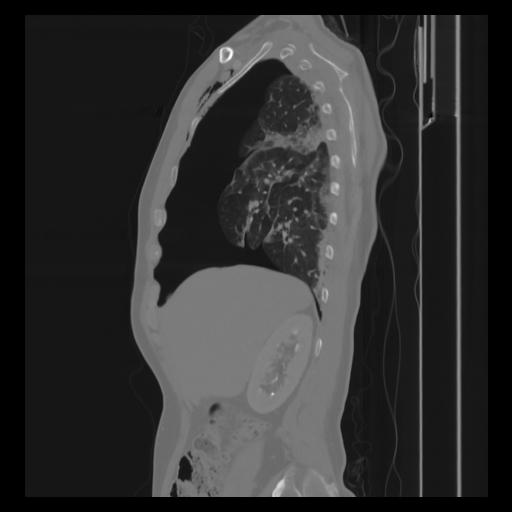

30 CUERPO,CE,Sagittal,3.000,CUERPO,Sagittal,